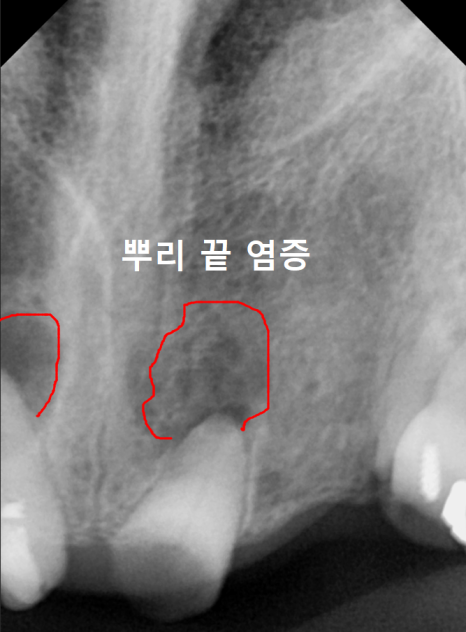

첫째로, 뿌리 끝에 염증이 생기면서

주변 잇몸뼈를 녹여버립니다.

나중에 임플란트를 하고 싶어도

심을 뼈가 없어서 치료가 어려워질 수 있어요.

파노라마와 CT를 통해 살펴보니

뿌리 끝에 염증이 가득 잡혀 있었죠.